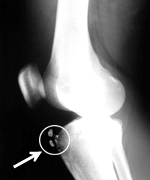

痛い! この経験者だけにわかるこの痛み! とりあえず語り合ってください ↓ オスグッターの場 http://mixi.jp/view_bbs.pl?id=12210917&comm_id=1524378 しかしオスグットなのでしょうかオスグッドなのでしょうか……。

オスグットについて語る